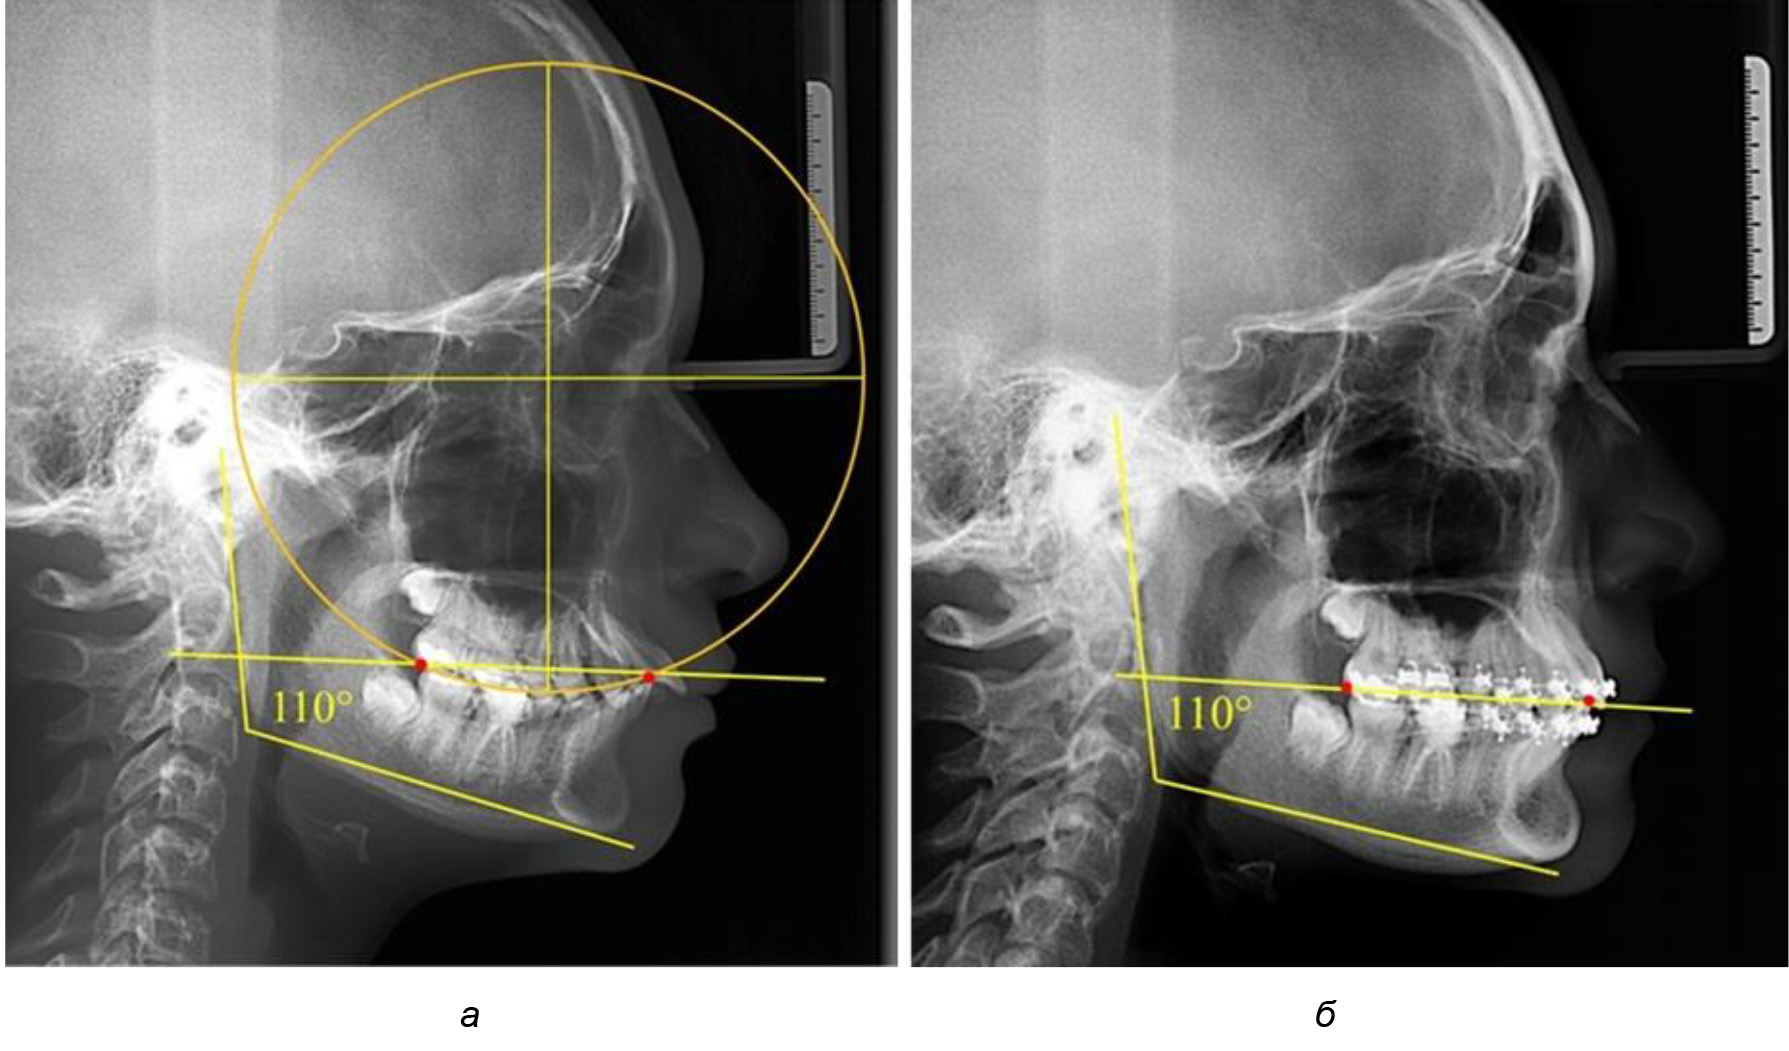

На рентгенограммах людей 2-й подгруппы (30 человек с нейтральным типом роста) величина угла нижней челюсти в среднем составила (120,34 ± 2,19) ° и характеризовала нейтральный тип нижней челюсти.

Глубина кривой Spee в среднем по 2-й подгруппе составил (3,54 ± 0,58) мм, что было незначительно меньше, чем при анализе аналогичного показателя 1-й подгруппы.

Достоверных различий с показателями, полученными при анализе ТРГ и ОПТГ, нами не отмечено (р ˃ 0,05). Деление величины радиуса круга к длине окклюзионной линии составило 1,612 ± 0,02, что, так же как и в 1-й подгруппе, было близким по значению к числу Фибоначчи (1, 618).

Рис. 3. Особенности кривой Spee на ТРГ (а) и ОПТГ (б) при нейтральном типе роста нижней челюсти